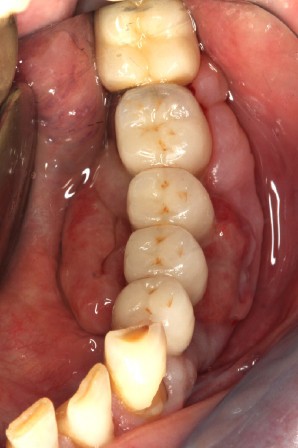

Question 1. Le carcinome épidermoïde, l’épulis et le granulome pyogénique peuvent a priori être évoqués tous les trois. La petite taille et le siège classiquement labial de l’hyperplasie endothéliale intravasculaire [4] permettent d’écarter ce diagnostic. Dans tous les cas, seul l’examen anatomopathologique permet d’étiqueter la lésion.

Le carcinome épidermoïde doit être évoqué du fait des caractéristiques de la lésion, de l’adénopathie sous-mandibulaire et du passé tabagique du patient.

L’épulis inflammatoire, pseudotumeur inflammatoire chronique, se développe généralement sur la gencive marginale ou sur une papille interdentaire. La lésion est habituellement sessile et mesure en moyenne 5 à 10 mm de diamètre. Il est indolore, érythémateux et rarement ulcéré. L’origine traumatique de l’épulis peut correspondre au cas présenté (espaces papillaires insuffisants).

Le granulome pyogénique (syn. botryomycome, hémangiome capillaire lobulé) est une lésion bénigne d’origine vasculaire [2]. Il siège sur la peau et, surtout, sur les muqueuses, en particulier les lèvres, les gencives, les joues et la langue. La lésion en bouche peut être unique ou multiple. Elle se présente comme un nodule saillant, souvent sessile, rarement pédiculé. La lésion est…